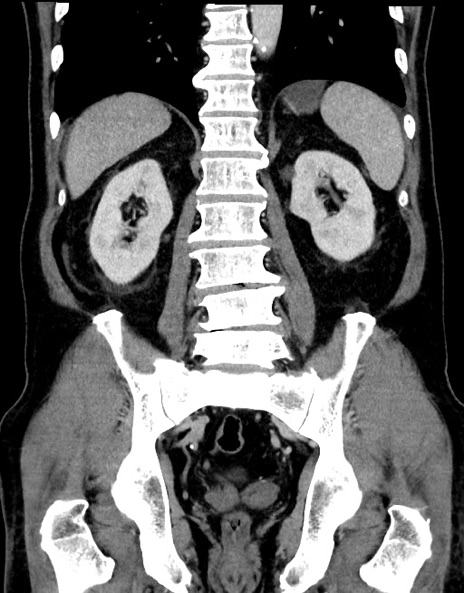

症例15(冠状断像)

【症例】70歳代男性

【主訴】腹痛

【現病歴】今朝から腹痛あり。全体的に痛い。特に左上の方。排ガスが今日はない。冷や汗が出る。

【既往歴】直腸癌術後

【身体所見】左側腹部〜上腹部に圧痛あり。腹膜刺激症状明らかなではない。軽度反跳痛。左下腹部に術後瘢痕あり。

【データ】WBC 7700、CRP 0.02